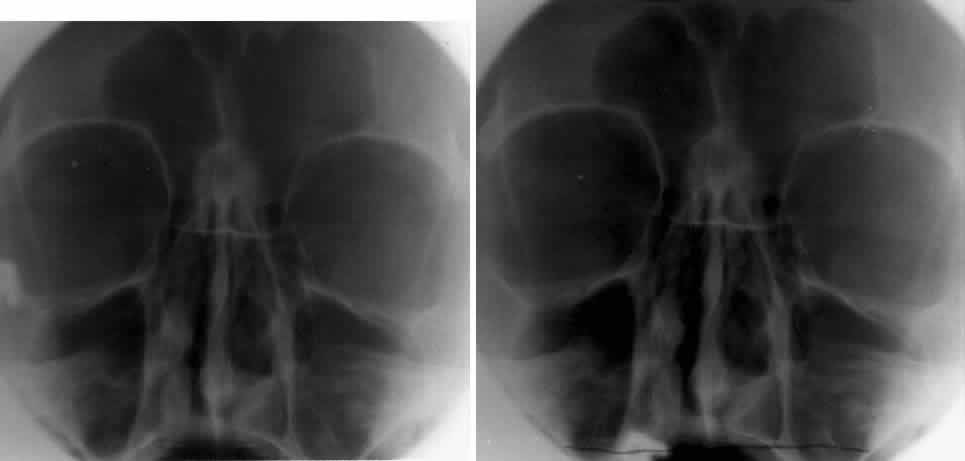

WATERS PROJECTION

In an attempt to improve the visualization of the maxillary and ethmoid sinuses, in 1915 Waters and Waldron7 described a radiographic projection (Fig. 2) that eliminated the overlapping shadows of the dense petrous ridge of the temporal bone. Waters projection is created by placing the chin of the patient on the x-ray cassette with the canthomeatal line (the line that connects the lateral canthus and the external auditory meatus) at 37 degrees to 45 degrees.5,6 This orientation is accomplished if the nose of the patient is approximately 0.5 to 1.5 cm above the x-ray plate.7,8 A mnemonic is—the patient raises the chin up to sip water.

Fig. 2. A. Schematic showing positioning for a Waters projection. (CM, canthomeatal line; CR, central ray) B. Radiograph of a Waters projection. The petrous ridge lies below the maxillary sinus. (a, frontal sinus; b, medial orbital wall; c, innominate line; d, inferior orbital rim; e, orbital floor; f, maxillary antrum; g, superior orbital fissure; h, zygomatic-frontal suture; i, zygomatic arch) (A; Rao VM, Gonzalez CF: Plain film radiography and polytomography of the orbit. In Gonzalez CF, Becker MH, Flanagan JC [eds]: Diagnostic Imaging in Ophthalmology, pp 1–7. New York, Springer Verlag, 1986)

Waters view provides the best image of the maxillary antrum and good images of the orbital rim, orbital floor, zygomatic bones and arches, lesser wing of the sphenoid, and infraorbital foramen. This view is useful to the clinician in orbital floor fracture assessment because of the clear image of the orbital floor and the underlying maxillary sinus. The floor of the orbit should form a continuous radiographic line with the lateral wall of the orbit. Confusion can occur regarding the location of the orbital floor and its relationship to the orbital rim. The orbital floor is located inferior to the orbital rim not in the same plane, because of the orientation of the patient's head in Waters projection. A soft tissue density in the roof of the maxillary sinus or opacification of the floor of the sinus suggests an orbital floor disruption.